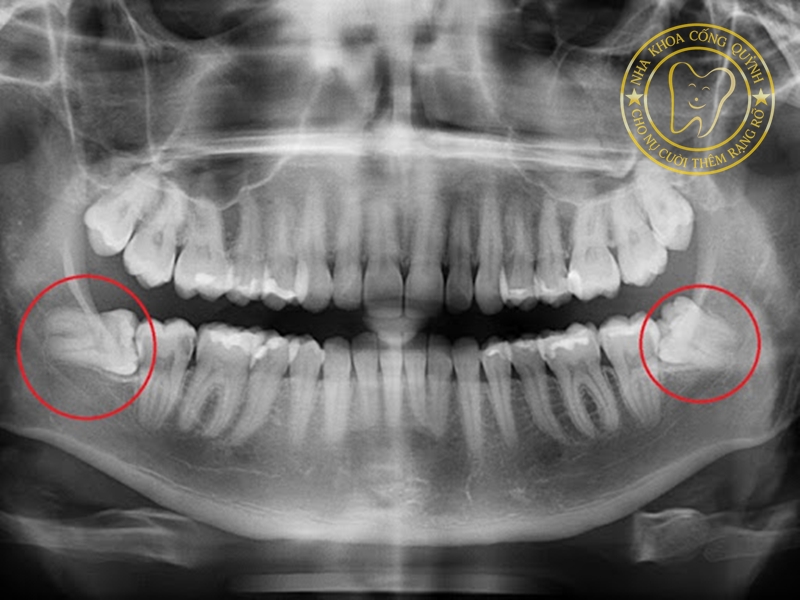

Răng khôn (răng số 8) thường mọc ở độ tuổi 17–25, khi xương hàm đã ổn định. Do không còn đủ khoảng trống, răng khôn dễ mọc lệch, mọc kẹt hoặc ngầm sâu dưới nướu, gây ra nhiều biến chứng ảnh hưởng sức khỏe răng miệng.

Máy chụp X-quang 3D ConeBeam đánh giá chính xác vị trí răng